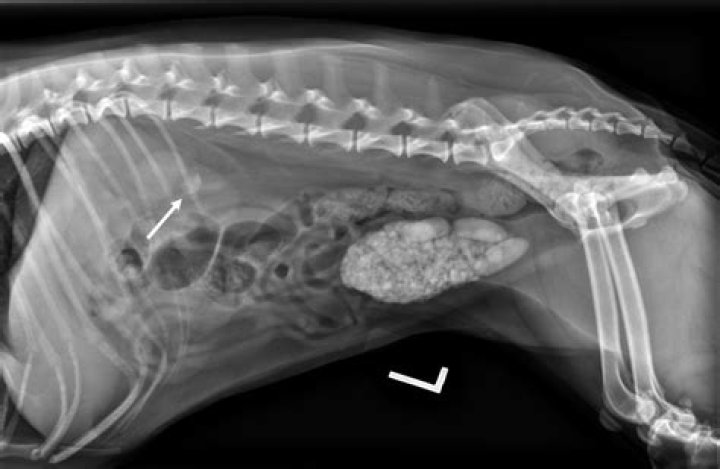

In senior dogs, there are many potential causes for loss of bladder control. Some of the more common are hormonal imbalance, weak bladder sphincter tone, urinary tract infections possibly involving stones, and spinal injuries or degeneration.

This can happen to dogs of any age. In senior dogs, there are many potential causes for loss of bladder control. Some of the more common are hormonal imbalance, weak bladder sphincter tone, urinary tract infections possibly involving stones, and spinal injuries or degeneration.